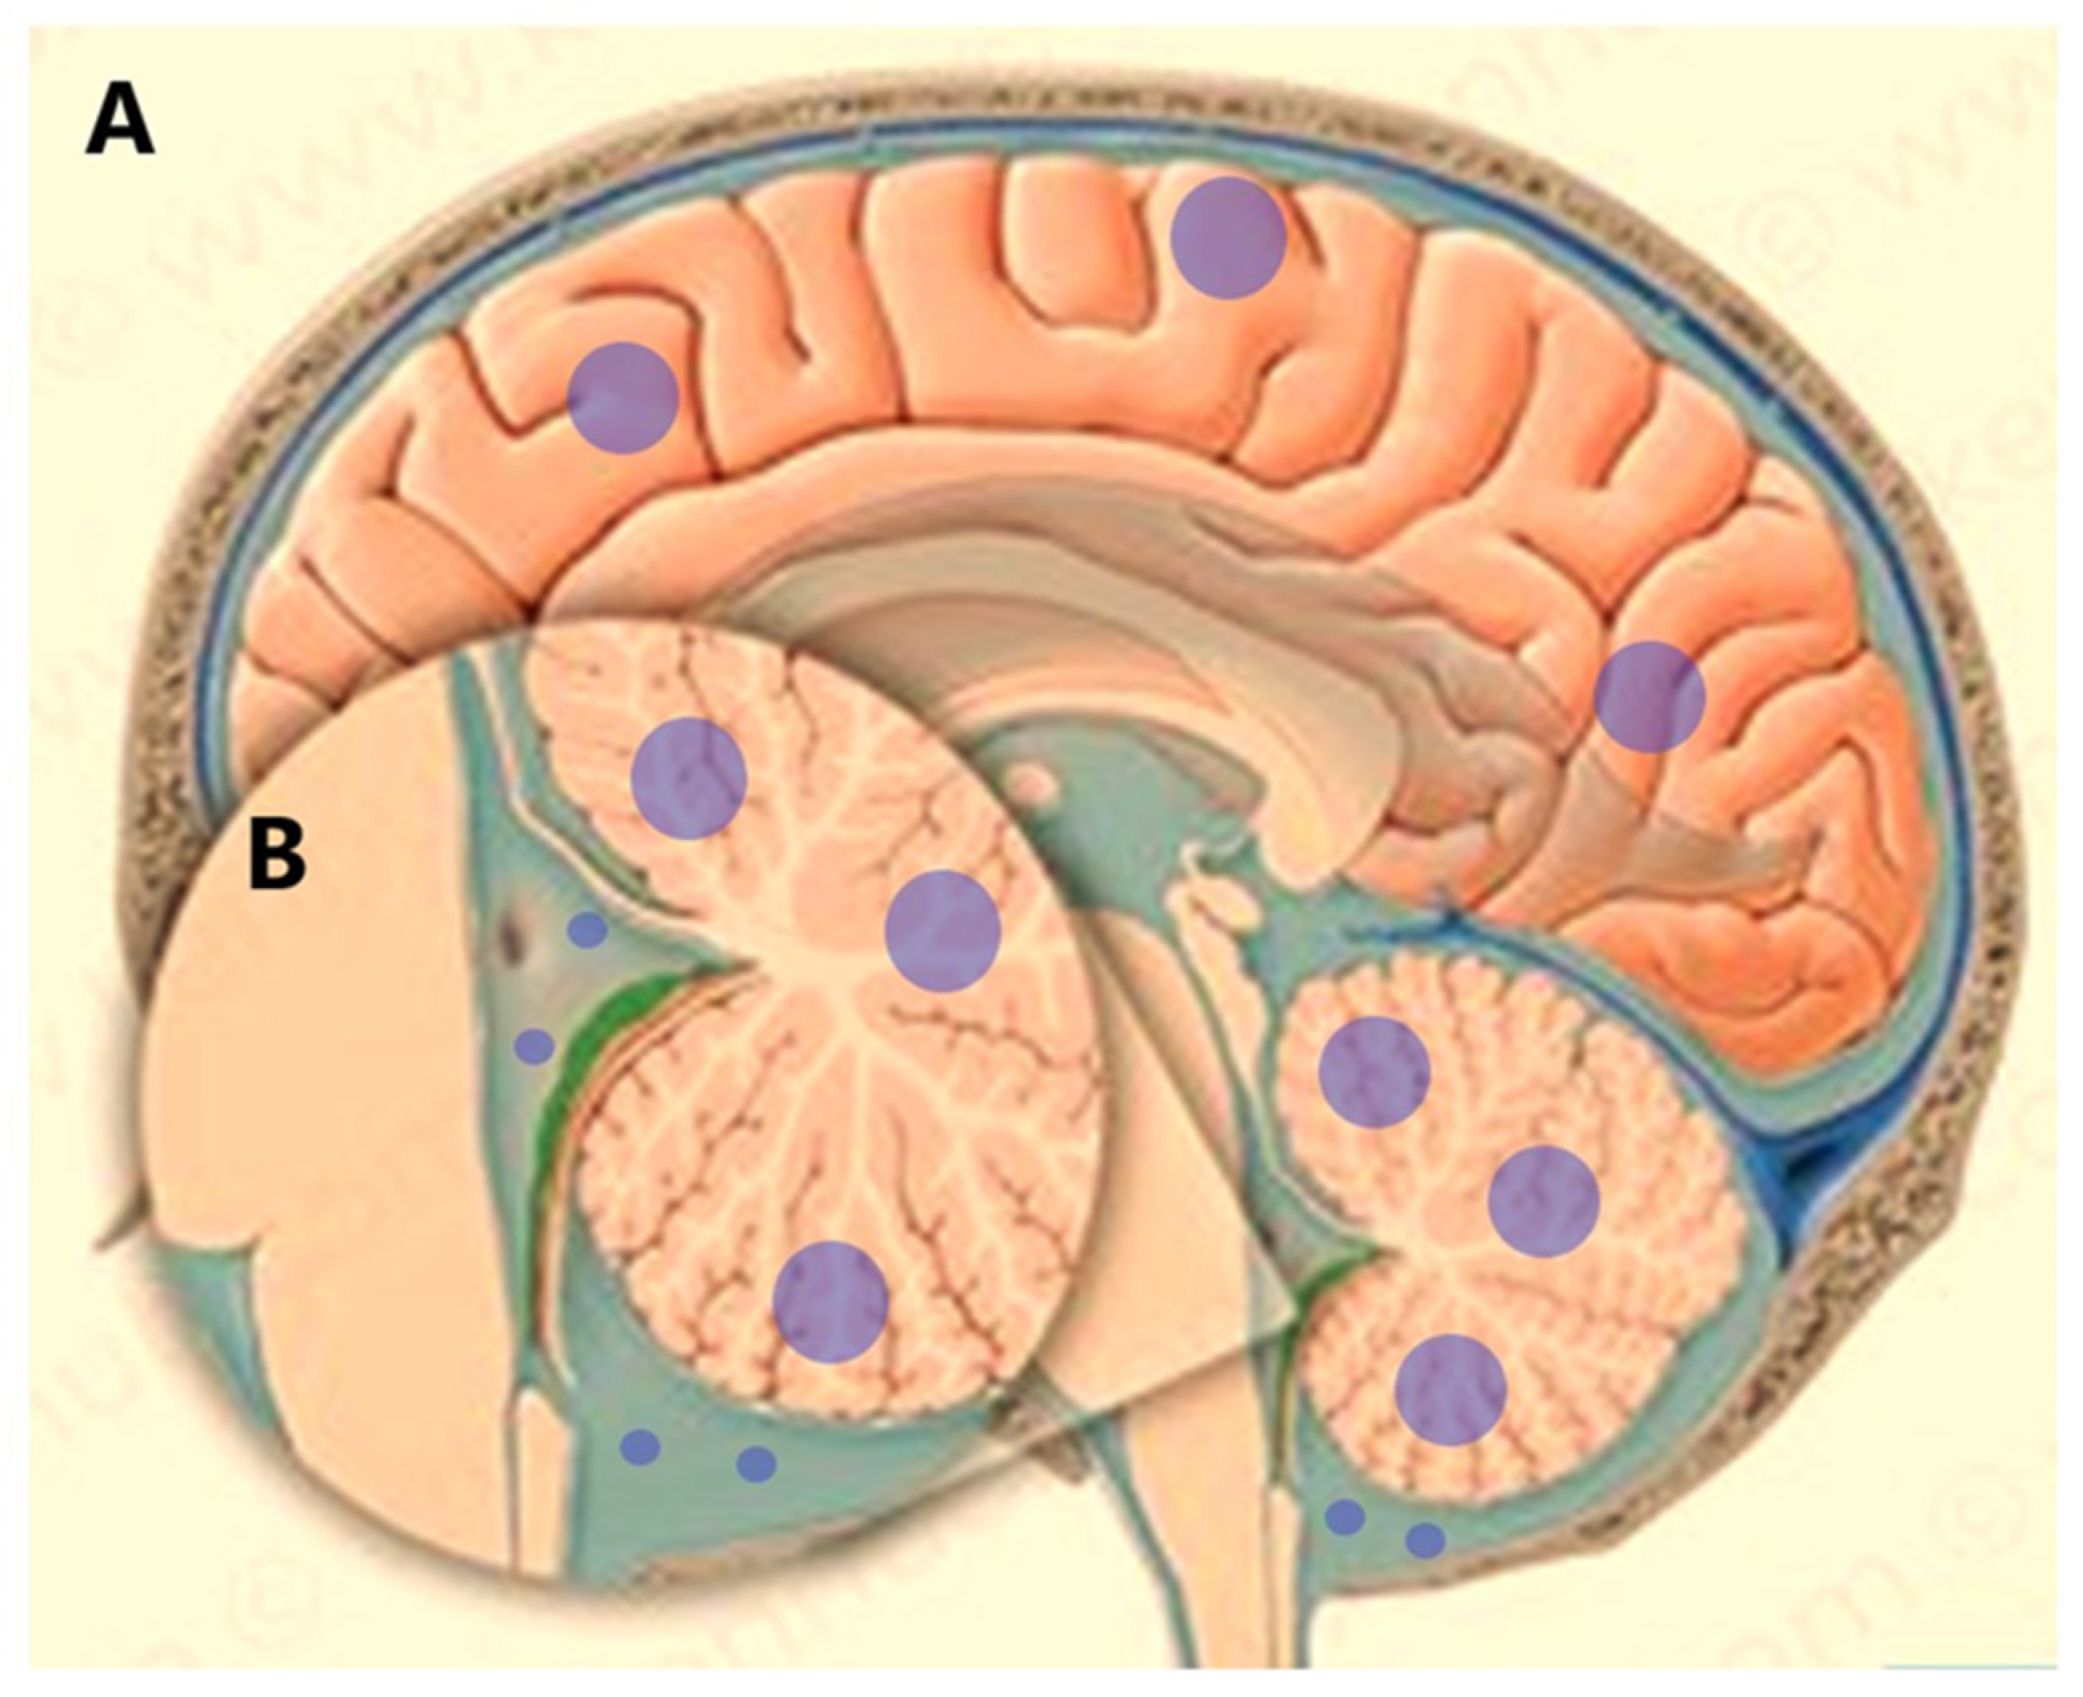

- Li, M.; Ren, X.; Jiang, H.; Yang, K.; Huang, W.; Yu, K.; Chen, H.; Dong, G.; Cui, Y.; Lin, S. Supratentorial high-grade astrocytoma with leptomeningeal spread to the fourth ventricle: A lethal dissemination with dismal prognosis. J. Neuro-Oncology 2019, 142, 253–261. [Google Scholar] [CrossRef]

- Pan, Z.; Yang, G.; He, H.; Yuan, T.; Wang, Y.; Li, Y.; Shi, W.; Gao, P.; Dong, L.; Zhao, G. Leptomeningeal metastasis from solid tumors: Clinical features and its diagnostic implication. Sci. Rep. 2018, 8, 10445. [Google Scholar] [CrossRef]

- Pellerino, A.; Brastianos, P.; Rudà, R.; Soffietti, R. Leptomeningeal Metastases from Solid Tumors: Recent Advances in Diagnosis and Molecular Approaches. Cancers 2021, 13, 2888. [Google Scholar] [CrossRef]